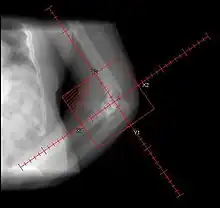

Heterotopic ossification of the elbow, after comminuted fracture and arthroplasty.

Heteropic ossification of the elbow, after comminuted fracture and arthroplasty.